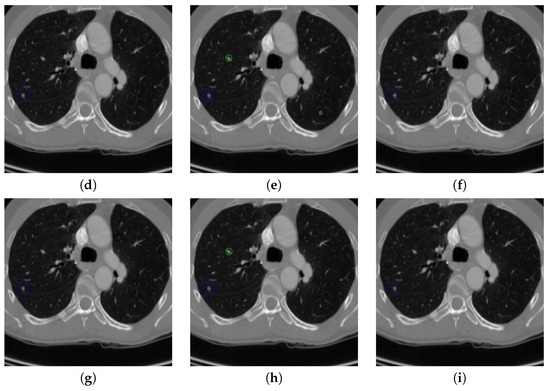

Figure 19. The result of detecting pulmonary nodules by different methods on one example image in TianChi dataset. Red circle represents the ground truth region of nodules, blue circles represent the correct estimation of pulmonary nodules, green circles represent the over-detected nodules, while yellow circles denote the nodules being omitted. (ai) are: ground truth nodule in the given chest CT image, nodule detected by 3D-FCN, MR-CNN, 3D-UNET, PRN-HSN, DCNN, CLAHE-SVM, MASK-RCNN and our proposed method.

Figure 17 and Figure 18 illustrates the performance of pulmonary nodule detection by different methods on two example images in the LUNA16 dataset. In addition, Figure 19 and Figure 20 illustrates the performance of pulmonary nodule detection by different methods on two examples images in the TianChi dataset. As marked by green circles in Figure 18b,c and Figure 19c, the 3D-FCN and MR-CNN directly detected the nodule candidates from the original CT image without pre-processing, resulting in the incorrect determination of non-nodule tissue outside lung as nodule since the outside-lung organs are not filtered out from the nodule candidates. The 3D-UNET and PRN-HSN add the lung parenchyma region segmentation stage before detecting the nodule candidates inside-lung, so they provide better performance than 3D-FCN and MR-CNN in decreasing the over-estimation rate. However, they still suffer from unsatisfactory results for the following reasons: (1) the lung parenchyma segmentation is generated by simple thresholding with morphological operations so the near-edge regions are lost, shown as the one marked by yellow circle in Figure 20d,e; (2) the convolution kernel used in nodule candidate detection of 3D-UNET is with a small receptive field to learn global features from the image, so it is likely to confuse some small tissues as true nodules with small sizes, shown as the one marked by green circle in Figure 18d and Figure 20d; and (3) the proposed hierarchical saliency network (HSN) in PRN-HSN for nodule candidate classification omits the information with different resolutions, resulting in that the small-size nodule within the weakened, low-resolution region cannot be correctly recognized, as shown by the yellow circle in Figure 18e. The DCNN method simply applies the Faster RCNN method to provide good performance with low computational cost, but it may omit the nodules on the parenchymal edge shown as yellow circles in Figure 20f. CLAHE-SVM method adds a contrast-enhancement pre-processing before the nodule detection, leads to better performance on detecting nodules in the low-contrast region. However, it is easily to over-enhance the small-size tissues and over-estimate them as nodules, as shown by the green circles in Figure 19g andFigure 20g. The detection is also implemented over the whole image, so the nodule on the parenchyma edge may be under-estimated show by the yellow circle in Figure 20g. The Mask-RCNN method provides better effects than the above methods because of the good performance of Mask-RCNN in object detection. However, the performance is not stable for the small-size tissues and the irregular-shape nodule, shown by the green circles in Figure 17h and Figure 19h, and the yellow circle in Figure 19h. The proposed method takes the advantage of a series of U-Net-like networks to perform the nodule detection following a “coarse-to-fine” order of inside-lung region detection, nodule candidate detection and nodule determination. The U-Net network is modified by embedding inception structure, replacing the convolution and pooling by dilated convolution, and adapting multi-scale pooling and multi-resolution convolution connection, for different requirements of the three stages, respectively. Moreover, it makes use of the MSE loss, VGG-19-based perceptual loss as the complement of dice loss to optimize the whole framework. Therefore, as shown in Figure 17i, Figure 18i, Figure 19i and Figure 20i, the proposed framework provides superior performance on pulmonary nodule detection with low over-estimation of non-nodule tissues at the same time.